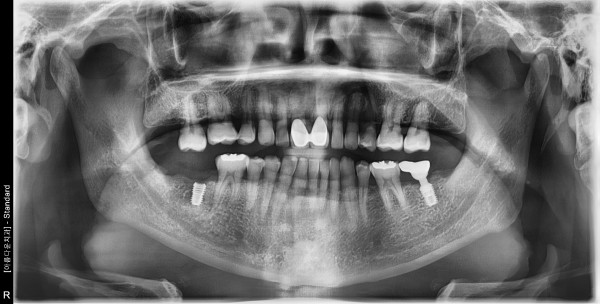

61세 남자 하악 좌,우측 구치부 치조골이식술 후 임플란트 식립